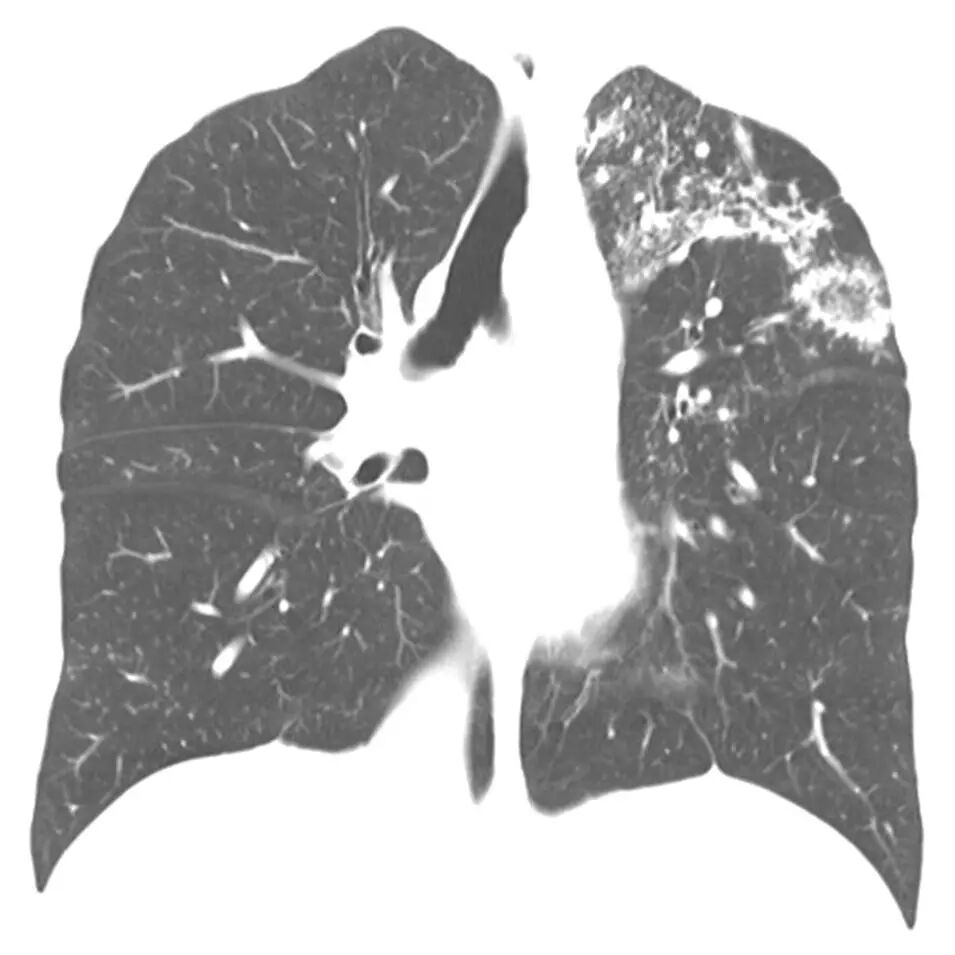

这是一个文献报道的例子,21岁小伙子干咳、低热盗汗2月,肺部影像有弥漫的磨玻璃影,但仔细看磨玻璃影里也有显著的弥漫微结节。支气管肺泡灌洗液(BALF)呈牛奶样,PAS(+)血TB抗体(+),T-SPOT(+),抗结核后6月后,肺部阴影吸收。[3]

我们将影像放大了看,和刚才所看的肺结核反晕征有一定相似性,也是由弥漫的微结节拼凑构成的。

在sPAP的病因方面,肺结核约占一半,有4例;另外接近一半是骨髓增生异常综合征(MDS),也是4例;还有1例是慢性髓细胞性白血病(CML)。在sPAP的肺CT中,仅1/3患者有小叶间隔增厚的表现,但肺结核及MDS患者,各有一半病例有散在微结节。

前面我们回顾了结核的病理,重要特征为肉芽肿、微结节。从上述病例可知,即使临床表现有所特殊,但如果我们有目的地去看,仍然有可能找到这些微结节的蛛丝马迹,为诊断提供线索。